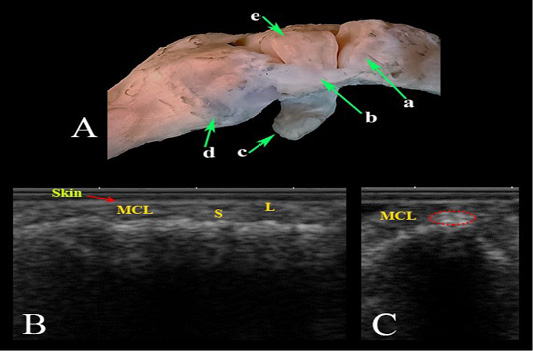

Medial collateral ligament of the carpal joint. (A) Photomacrograph. Ultrasonographic imaging: (B) LS, (C) TS. a- Radius; b- Medial collateral ligament; c- Accessory carpal bone; d- Metacarpal bones; (e) Radial carpal bone; MCL- Medial collateral ligament; L- Long fibers; S- Small fibers.